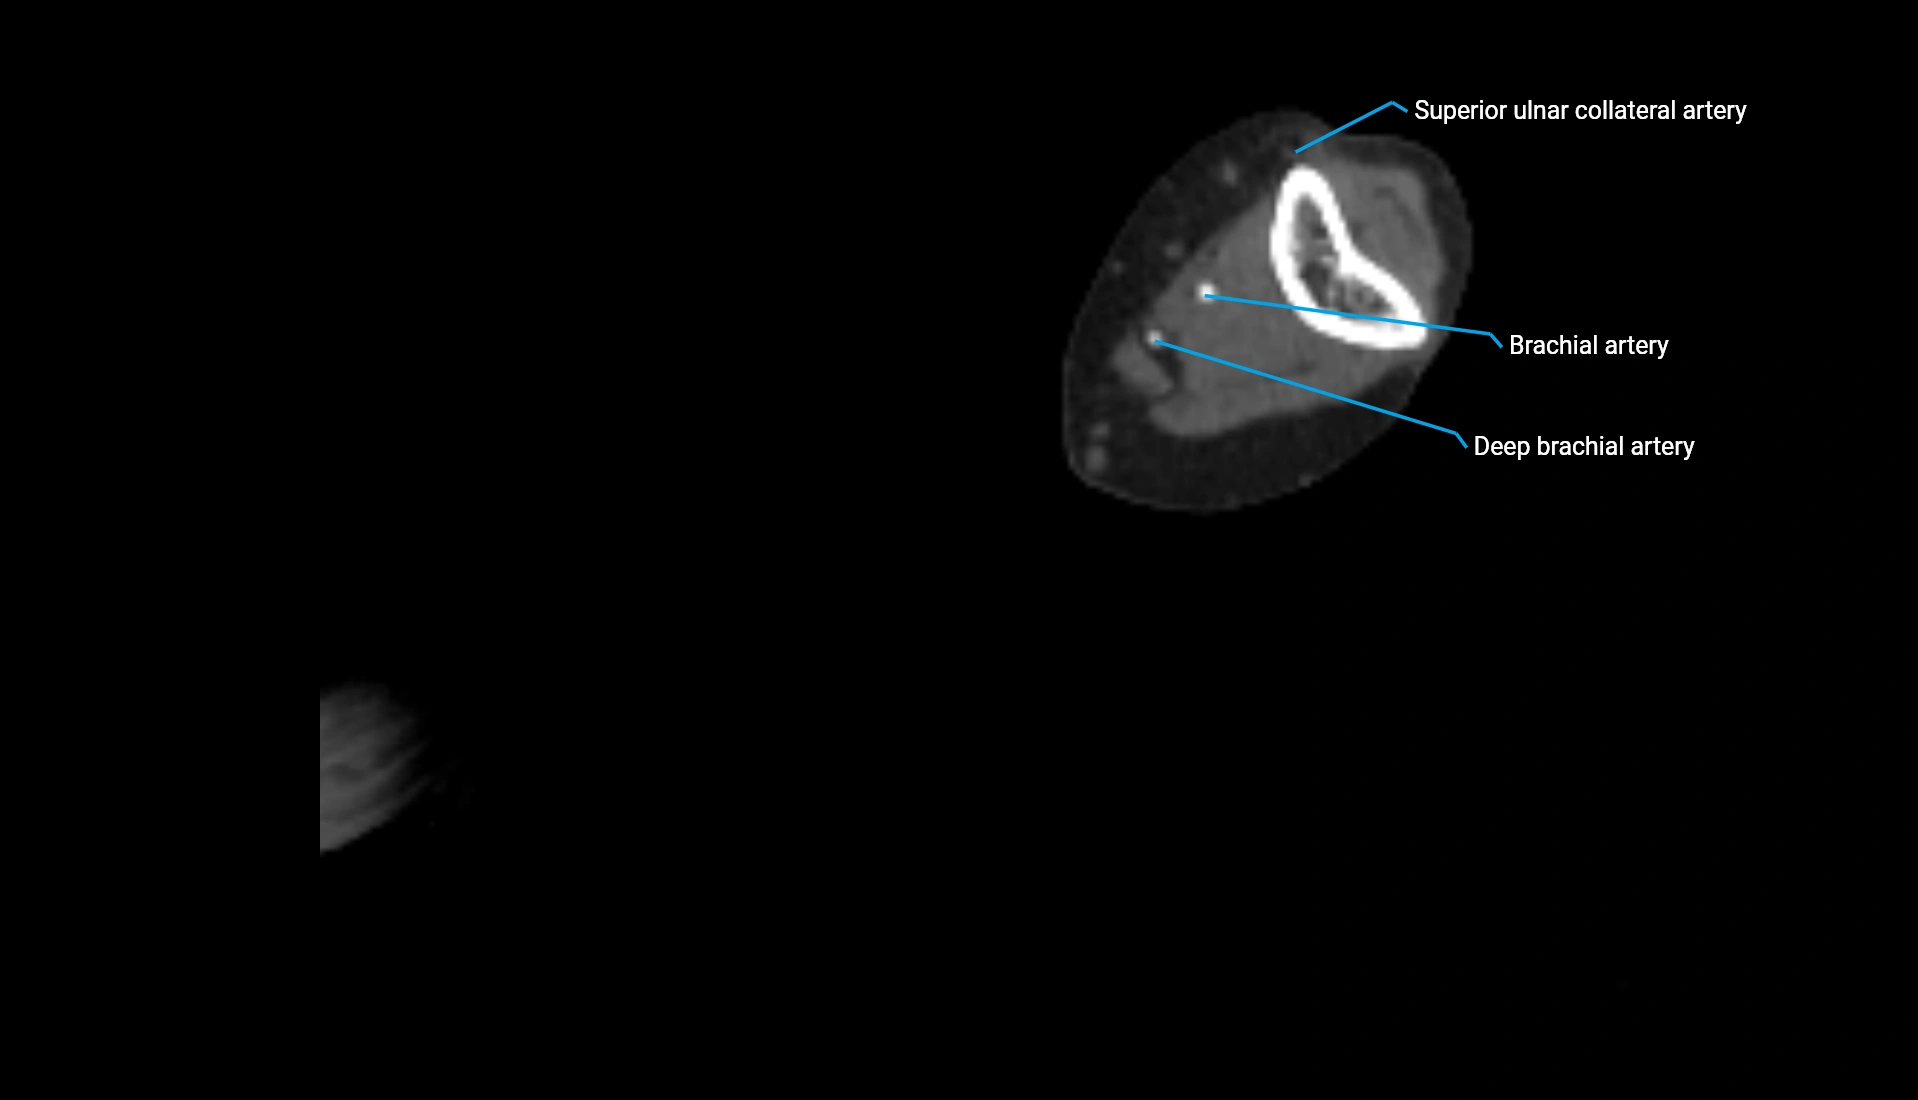

CT Appearance

Non-Contrast CT:

• Cortex: High-density, sharply defined

• Subchondral bone: Dense cancellous matrix

• Articular surface: Smooth concave contour articulating with the capitellum

• Excellent for evaluating bone integrity, alignment, and subtle fractures